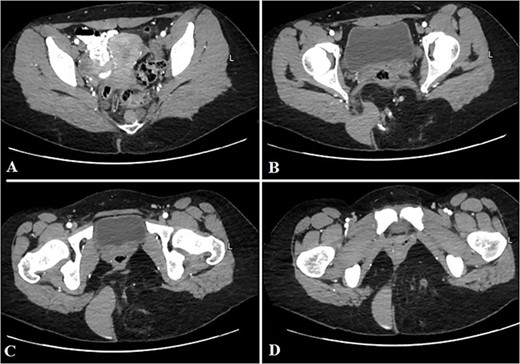

Contrast-enhanced computed tomography (CT) showed an ill-defined mass-like lesion in the gluteal region. The lesion consists of mixed tissue (fat predominantly, fluid and calcifications) and is seen exerting mass effect on the adjacent muscles and extending into the ischioanal, ischiorectal fossa and pre-coccygeal region (Figs 1 and 2).

Selected sagittal CT cuts of the pelvis with oral and IV contrast (Venous phase) from left to right sides of the body (A–D), showing the mentioned gluteal mass. The cystic component of the mass is noted at the right gluteal region and the pre-coccygeal portion is well shown in C.